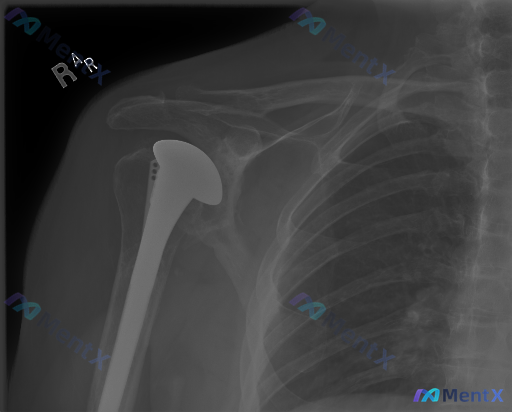

整理了一张右肩关节正位X光片的病例资料,先看影像描述: - 右肩已行肱骨头置换术,金属假体柄延伸至髓腔,假体头位置居中 - 假体柄与骨皮质接触紧密,未见明显假体周围骨折线或透亮线 - 肩胛盂及肩峰形态基本完整,但肩胛盂关节面下方可见骨质硬化及骨赘形成 - 肩关节周围软组织轮廓尚可,肩峰下及大结节区域...